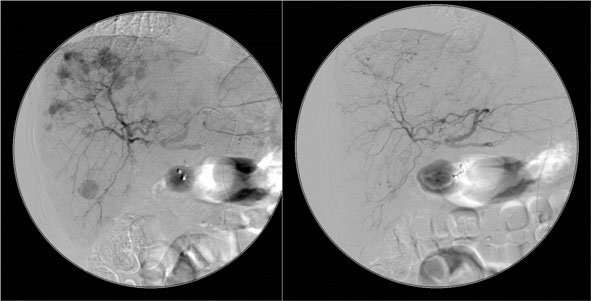

• Chemoembolisationen